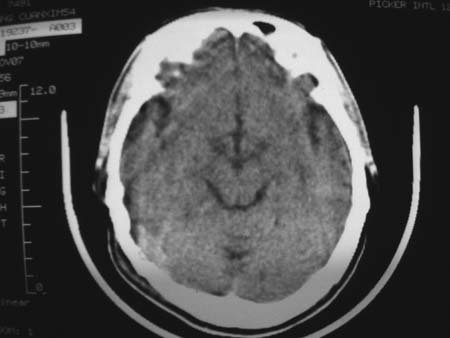

男,54岁,十天前被钢管打伤头顶部,现自述头部不适,视物模糊,并于两天前发觉右枕部有包块,既往未有明显异常.

颅骨多处骨质不完整,内板变薄,右侧额颞部局部呈“穿凿样”骨质缺损,相应区硬膜外密度略增高。多考虑:骨嗜酸性肉芽肿!

右枕骨及双额角均有类似改变,考虑骨髓瘤可能性大,建议查本周氏蛋白.

颅骨多处骨质不完整,内板变薄,右侧额颞部局部呈“穿凿样”骨质缺损,相应区硬膜外密度略增高。多考虑:骨髓瘤或骨嗜酸性肉芽肿!

颅骨多处骨质不完整,内板变薄,右侧额颞部局部呈“穿凿样”骨质缺损,相应区硬膜外密度略增高。多考虑:骨髓瘤或骨嗜酸性肉芽肿!10天前受伤,不会在2天前才发现头部包块,估计与外伤无关.